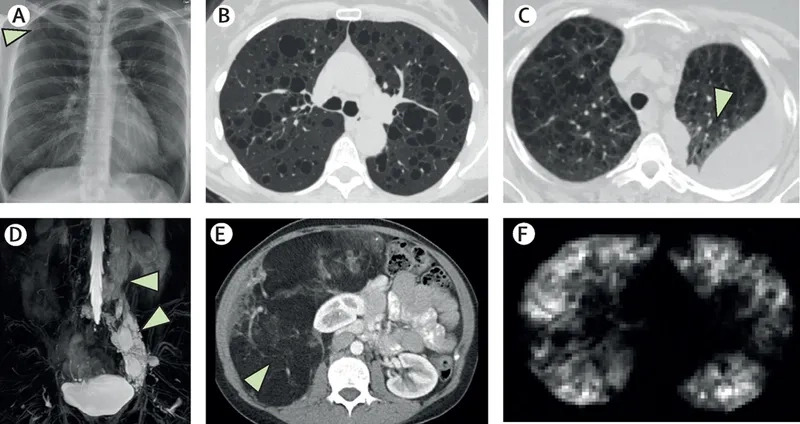

• This condition can occur sporadically or in direct association with a genetic disorder known as tuberous sclerosis complex (TSC), which also involves benign tumors.

• Progressive shortness of breath in women, especially during physical activity or exertion, is the most common and defining of all LAM symptoms.

• Recurrent collapsed lungs (pneumothorax) and a milky fluid buildup around the lungs (chylothorax) are serious complications that often require immediate medical attention.

• Other potential signs include benign kidney tumors (angiomyolipomas), a persistent cough, chest pain, and fatigue, which can impact daily quality of life.